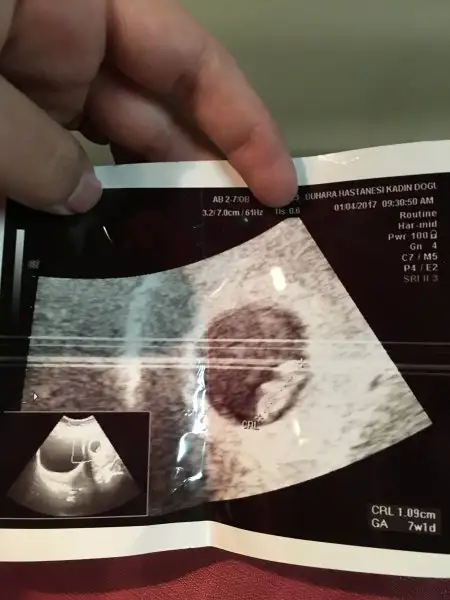

buna gore erkek canım. benım karından boyleydı doktor kıza benzıyor dedı. kesındegıl benımkıde ama kesnlesırse teorı bnde tuttuEki Görüntüle 1939188 Eki Görüntüle 1939187 Kizlar banada baksanizaa altan utrasyon yani vajenden

Kızlarr nerdesiniz cevap yok muEki Görüntüle 1939127 Eki Görüntüle 1939128 Kızlar bana da bakar mısınız karından ultrason ve üstteki 9 hafta alttaki 7 haftalık